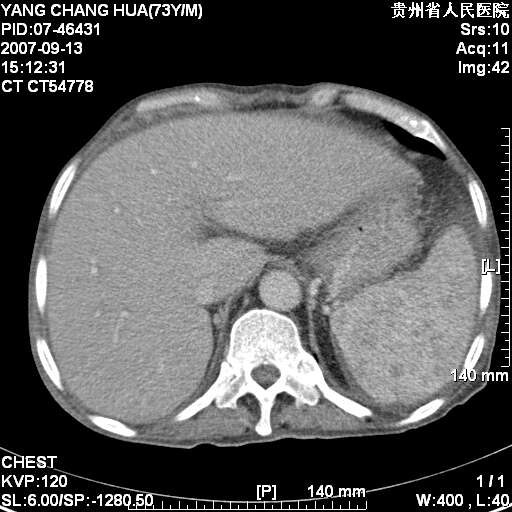

图像没有传全。肺部为感染性病灶;肺囊肿;双侧胸腔积液;肝脾肿大;腹水。

双肺部为感染性病灶.双侧胸腔积液;肝脾肿大;腹水.

双肺部为感染性病灶.双侧胸腔积液;肝脾肿大;脾脏密度不均,不除外脾侵润?腹水.

双肺部为感染性病灶.双侧胸腔积液;肝脾肿大;腹水

图片不全.就这几张图片.无法诊断淋巴瘤的,我考虑:双肺部为炎性病灶.双侧胸腔积液;肝脾肿大;腹水

双肺点片状影,以双上肺改变明显.双侧胸腔积液.为感染性病灶,但不除外结核.

肝脾都大..

肝脾肿大。

少量腹水。

双肺散在斑片状及多发小结节状阴影,边缘模糊,双上肺野明显,双侧胸膜腔少量积液,纵隔及肺门区未见明显肿大淋巴结,肝脾肿大,脾内见多发低密度区,结合临床考虑恶性淋巴瘤(肺内表现为肺炎肺泡型),单看影像表现,肺结核不能排除。建议结合实验室检查或表浅淋巴结活检。